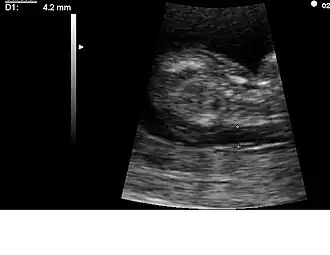

A partir de 1979 se dispone en los laboratorios de una prueba en sangre que permite establecer una sospecha diagnóstica para varios defectos congénitos (espina bífida y otros defectos del tubo neural). Esta prueba es la determinación de los valores de AFP (alfa-fetoproteína), que se encuentran aumentados en los embriones que presentan estos trastornos del desarrollo. Varios años después se establece una relación estadística entre valores bajos de esta proteína y la aparición de trastornos cromosómicos, en especial del SD. En años posteriores se descubrieron algunas asociaciones similares con otras sustancias en sangre materna. Hoy día es común la determinación de AFP, estriol y hCG (Gonadotropina coriónica humana) para determinar el riesgo de aparición del SD. A esto se le llama «triple prueba». Algunos laboratorios incluyen la determinación de inhibina (cuádruple prueba). Los valores de estas sustancias en sangre, así como datos acerca de la edad materna y los antecedentes personales y familiares permiten calcular un riesgo de aparición de SD, pero no suponen un diagnóstico de certeza. Determinadas mediciones que se realizan durante las ecografías (longitud del fémur, grosor del pliegue nucal, y otras) también aportan información para el cálculo de ese riesgo, pero tampoco permiten establecer el diagnóstico definitivo.

La técnica más frecuentemente utilizada para la obtención de material genético fetal es la amniocentesis. Esta técnica se empezó a generalizar en la década de 1960, y consiste en la punción ecoguiada de la cavidad amniótica por vía abdominal. Se consigue así una muestra de líquido amniótico, de donde es posible obtener células fetales para su estudio. Debe realizarse preferentemente entre las semanas 14 a 17 del embarazo. Es una técnica relativamente inocua y poco molesta, pero comporta un riesgo del 1-2 % de aborto, lesión fetal, o infección materna.